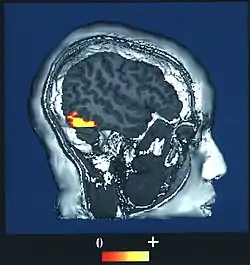

Brain imaging studies typically show a great deal of activity in an area of the temporal lobe known as the fusiform gyrus, an area also known to cause prosopagnosia when damaged (particularly when damage occurs on both sides). This evidence has led to a particular interest in this area and it is sometimes referred to as the fusiform face area (FFA) for that reason.[10]

The fusiform face area (BA37— Brodmann area 37) is located in the lateral fusiform gyrus. It is thought that this area is involved in holistic processing of faces and it is sensitive to the presence of facial parts as well as the configuration of these parts. The fusiform face area is also necessary for successful face detection and identification. This is supported by fMRI activation and studies on prosopagnosia, which involves lesions in the fusiform face area.[34][35][36][37][38]

The occipital face area is located in the inferior occipital gyrus.[35][38] Similar to the fusiform face area, this area is also active during successful face detection and identification, a finding that is supported by fMRI and MEG activation.[34][38] The occipital face area is involved and necessary in the analysis of facial parts but not in the spacing or configuration of facial parts. This suggests that the occipital face area may be involved in a facial processing step that occurs prior to fusiform face area processing.[34][38]

One study used BOLD fMRI mapping to identify activation in the brain when subjects viewed both cars and faces. They found that the occipital face area, the fusiform face area, the superior temporal sulcus, the amygdala, and the anterior/inferior cortex of the temporal lobe all played roles in contrasting faces from cars, with initial face perception beginning in the fusiform face area and occipital face areas. This entire region forms a network that acts to distinguish faces. The processing of faces in the brain is known as a "sum of parts" perception.[49]